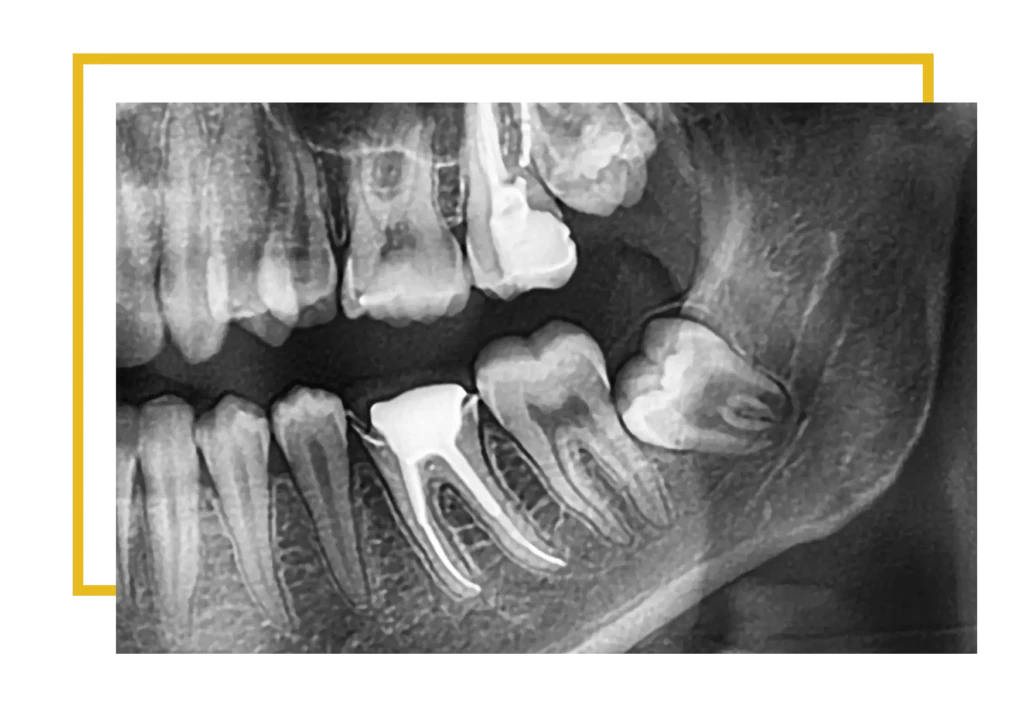

Całkowicie zatrzymana ósemka pozostaje w całości ukryta w kości i nie jest w ogóle widoczna w jamie ustnej. Najczęściej Pacjenci dowiadują się o niej w trakcie rutynowej kontroli RTG — gdy wykonywany jest pantomogram lub tomografia komputerowa. Choć może nie dawać objawów przez wiele lat, nie oznacza to, że jest nieszkodliwa. Taki ząb może prowadzić do powstawania torbieli, uszkodzenia korzeni sąsiednich zębów lub przewlekłych stanów zapalnych. Właśnie dlatego należy go usunąć jak najszybciej.